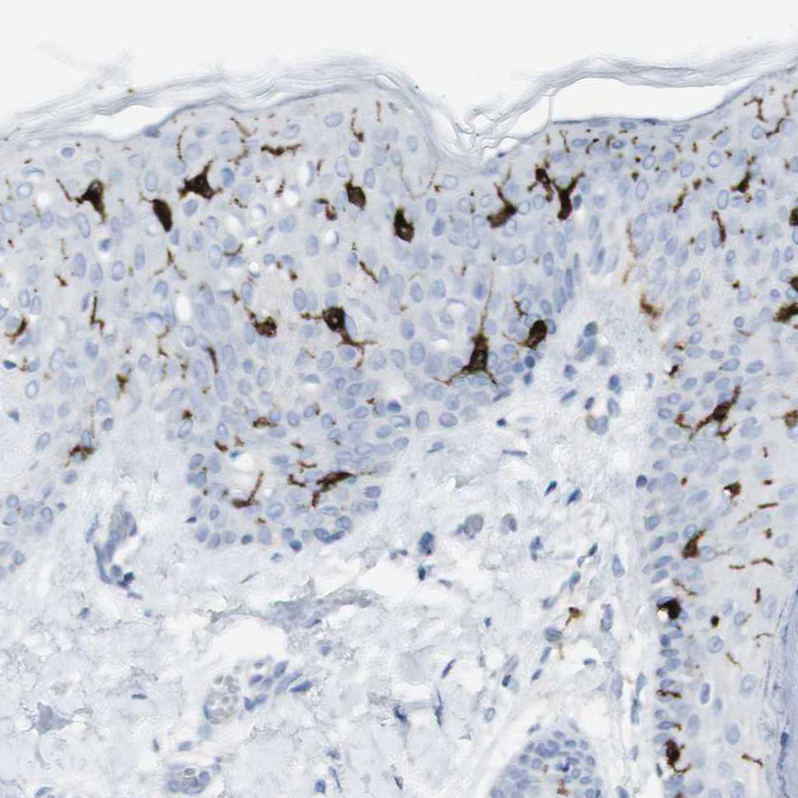

Immunohistochemistry analysis in human skin and pancreas tissues using HPA011216 antibody. Corresponding CD207 RNA-seq data are presented for the same tissues.